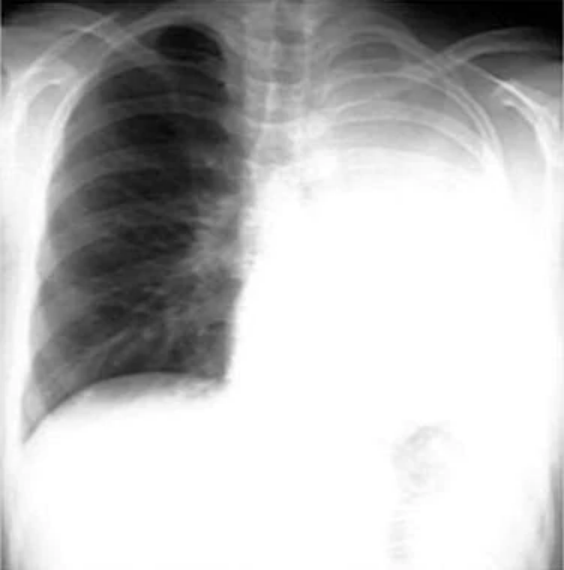

非小细胞肺癌。左上塌陷几乎总是继发于支气管内支气管癌。